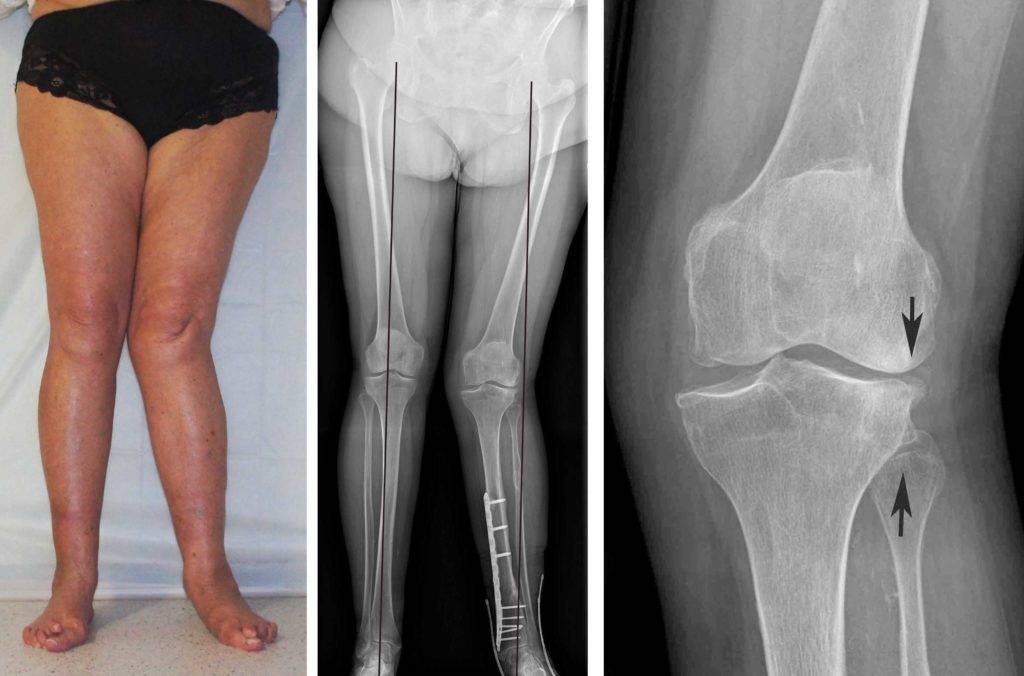

В запущенных случаях патология в росте конечностей приводит к положению, как на фото. Происходят изменения в верхнем отделе голени и берцовой кости, появляется внутренняя ротация голени, возможно развитие плоскостопия и слабости голеностопных мышц.

В ходе оперативного вмешательства врачи удаляют фрагменты большеберцовой и бедренной костей, после чего устанавливают аппарат Илизарова. Прооперированные участки фиксируют пластинами и винтами или ставят металлические рамы снаружи конечности (на фото). При нестабильности коленного сустава дополнительно проводят пластику связок.

Рентген показывает определенные изменения:

- Образуется клювовидное деформирование большеберцовой кости. Патология локализуется в верхнем участке метафиза или области между ним и эпифизом.

- Поверхность суставного сочленения кости изогнута внутрь и скошена. Высота эпифиза изнутри втрое ниже нормального размера, наблюдается краевое дробление.

- Ростковая зона изнутри расширяется, костные пластинки с нечеткими границами. У подростков диагностируют преждевременно закрытую зону роста кости.

- Из-за ротации проекции мало- и большеберцовой костей на снимке накладываются друг на друга.